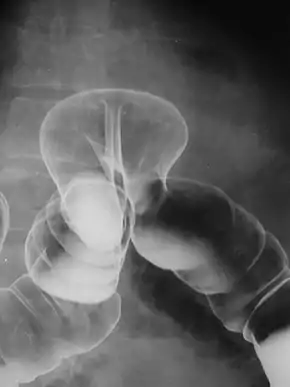

Radiograph of a barium enema displaying a colonic herniation.

A lower gastrointestinal series is a medical procedure used to examine and diagnose problems with the human colon of the large intestine. Radiographs (X-ray pictures) are taken while barium sulfate, a radiocontrast agent, fills the colon via an enema through the rectum.